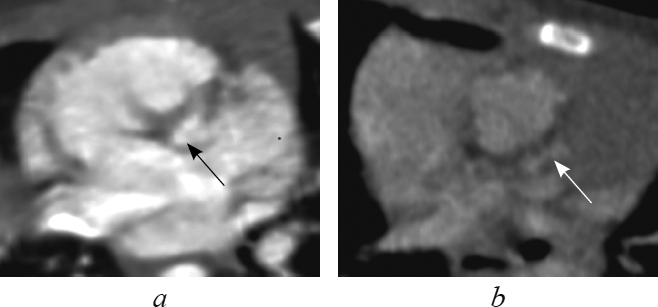

Анатомические признаки ушка, характерного для морфологически правого предсердия (треугольная форма с тупой вершиной, широкое соединение с предсердной полостью, слабо выраженная дольчатость [1, 2, 4, 16]), определяют в реформации по длинной оси приносящего тракта правого желудочка (рис. 1). В этой реформации видно, что при транспозиции морфологически правое предсердие соединяется с морфологически правым желудочком (см. рис. 1, а), а при корригированной транспозиции морфологически правое предсердие — с морфологически левым желудочком (см. рис. 1, b).

Рис. 1. В реформации по длинной оси приносящего тракта правого желудочка ушко морфологически правого предсердия при транспозиции магистральных сосудов (а, стрелка), при корригированной транспозиции магистральных сосудов (b, стрелка)

Fig. 1. Long-axis of right ventricle inflow tract reformation. The eyelet of the morphologically right ventricle in great arteries transposition (a, arrow) and in corrected great arteries transposition (b, arrow)